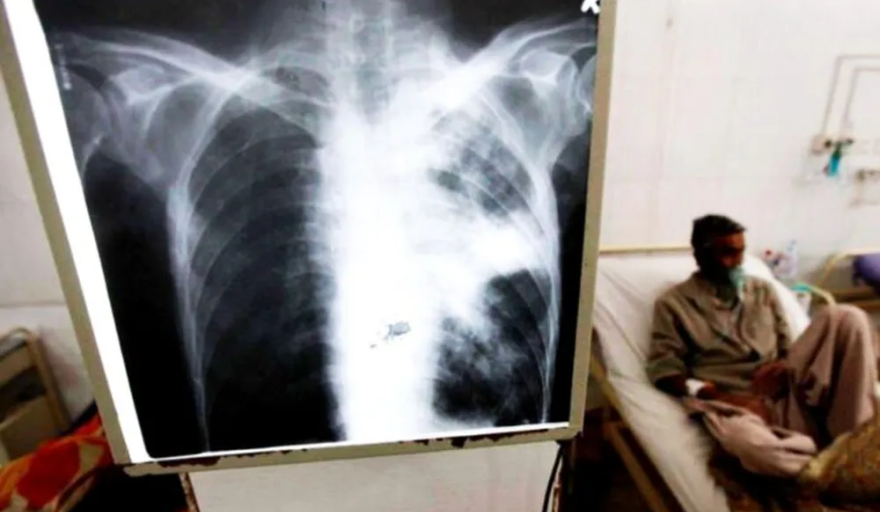

La tuberculosis - según describe el Ministerio de Salud bonaerense - es una enfermedad infectocontagiosa, causada por una microbacteria denominada Mycobacterium tuberculosis, conocida como “Bacilo de Koch” en honor a su descubridor, Roberto Koch, en el año 1882.

Se trata de una enfermedad curable, de notificación obligatoria, prevenible y de tratamiento gratuito, que afecta a los pulmones pero también puede dañar otros órganos como ganglios, cerebro y columna vertebral. Es importante el diagnóstico temprano y realizar un tratamiento completo con antibióticos sin interrupciones.